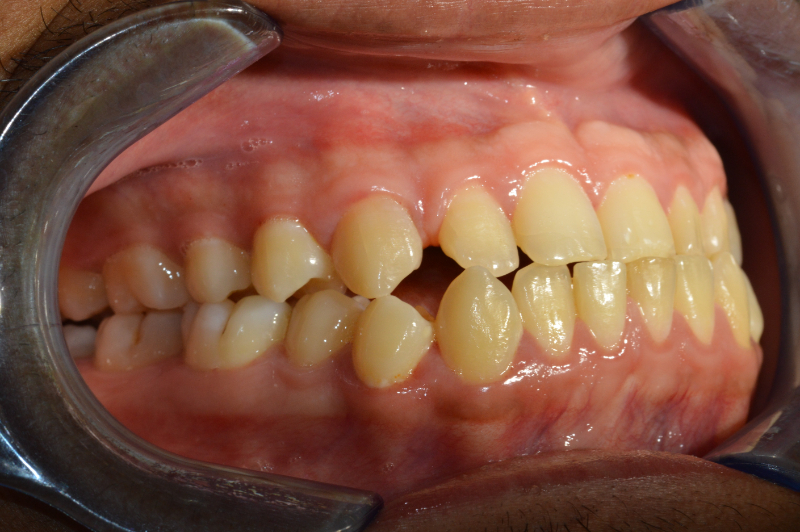

Prima

Il paziente, di 27 anni, si presenta alla mia osservazione già in trattamento ortodontico, a causa di un evidente morso inverso, manifestazione tipica di una terza classe dento-scheletrica.

In collaborazione con il Dott. Laganà e l’ortodontista Di Benedetti, è stato effettuato un attento studio del caso. Si è deciso di completare la fase di decompensazione ortodontica, spiegando al paziente che in questa fase avrebbe assistito ad una temporanea accentuazione del difetto estetico e funzionale, necessaria per garantire il successo della fase chirurgica.